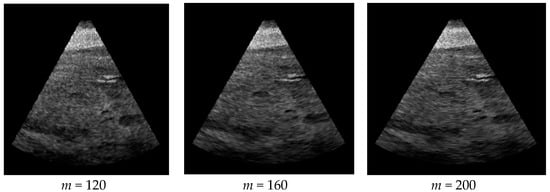

For experimental work presented in the paper, the reference images of real ultrasound images were sourced from the online ultrasound image gallery [7]. These are ultrasound scans of the liver, and have very similar image features, intensity distribution and noise content. Figure 1 shows three such reference images. The texture features extracted from these images will be compared in later sections with those of the generated synthetic images.

The feature vector given in Equation (6) was computed for the three reference images in Figure 1, and the average of the three sets were used as the reference feature vector. These values are given below:

VRef = {447.3, 597.3, 508.7, 433.7, 691.7, 435.3, 459.3, 290}

Figure 1. Reference ultrasound images [7] used in our work.